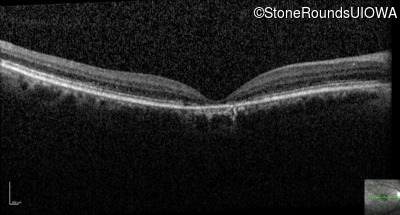

Optical Coherence Tomography - Left - 20/125

Exemplar / OCT Stack